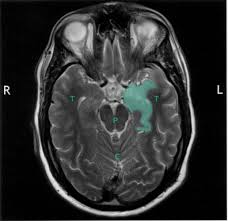

Brain mri—increased t2 signal intensity in frontotemporal region → viral (hsv) encephalitis.

In children older than 3 months and in adults brain biopsy: Herpesviral encephalitis, or herpes simplex encephalitis (hse), is encephalitis due to herpes simplex virus. • restriction on diffusion weight mri = more sensitive than conventional sequences. Misra uk, hashmi aa, kalita j. Diagnostic uncertainty and empirical management in pcr negative encephalitis. It is a severe condition brain mri may show limbic encephalitis (55) or diffuse t2 and dwi hyperintensities in the white matter, associated with restricted diffusion (54). Herpes simplex encephalitis occurs as 2 distinct entities: Mri is the imaging of choice in suspected cases of viral encephalitis, although ct scanning may be used where mri facilities are not available. The patient had initially improved after medical treatment. Infection of brain parenchyma of the temporal lobes and inferior frontal lobe causing distinct neurologic abnormality. Dhawan a, kecskes z, jyoti r, kent al. Associated with hsv encephalitis (strong evidence). In addition, because of the involvement of the.

It is a severe condition brain mri may show limbic encephalitis (55) or diffuse t2 and dwi hyperintensities in the white matter, associated with restricted diffusion (54). Brain mri—increased t2 signal intensity in frontotemporal region → viral (hsv) encephalitis. Associated with hsv encephalitis (strong evidence). Provided cranial imaging has excluded any contraindications such as a space occupying lesion or severe cerebral oedema and brain shift, a csf. Having said that, mri with contrast is considered the most sensitive imaging modality, and findings are present in over half of individuals 8. In addition, because of the involvement of the. We performed volumetric measurements of the left and right temporal lobes and of cerebral oedema. Herpes simplex encephalitis occurs as 2 distinct entities: The study analysed serially acquired magnetic resonance images (mri), of patients with acute hsv encephalitis who had neuroimaging repeated within four weeks of the first scan. Pregnancy the most common cause of encephalitis in newborns is vaginal delivery from a mother who is infected with herpes simplex virus 2 (hsv 2). There is no particular age, sex, or seasonal predilection. Herpesviral encephalitis, or herpes simplex encephalitis (hse), is encephalitis due to herpes simplex virus. Severe infection, particularly untreated herpes simplex virus (hsv) encephalitis, can cause brain hemorrhagic necrosis.

Alpha coma in japanese encephalitis. Herpes simplex encephalitis occurs as 2 distinct entities: Brain mri—increased t2 signal intensity in frontotemporal region → viral (hsv) encephalitis. A case of granulomatous hsv encephalitis: Encephalitis caused by hsv type 1 is rare but can result in significant brain damage or death. Contrast enhancement is uncommon during the first week of the disease. The study analysed serially acquired magnetic resonance images (mri), of patients with. Its symptoms are fever, confusion, coma, and seizures. Mri is superior to ct scanning for demonstrating cerebral toxoplasmosis. Brain mri is shown in fig. Having said that, mri with contrast is considered the most sensitive imaging modality, and findings are present in over half of individuals 8. Associated with hsv encephalitis (strong evidence). There is no particular age, sex, or seasonal predilection.